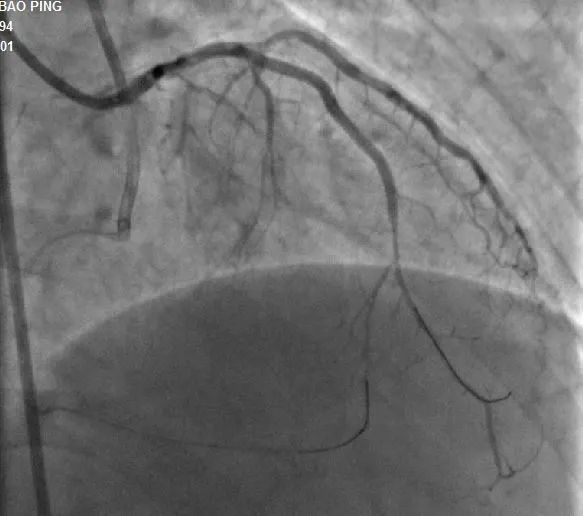

▲前降支CTO顺利开通

手术过程:7F LA1.0指引导管到位RCA开口,SionBlue(0.014”、0.5g)导丝送至后降支(PD3 )作为逆向导丝进入间隔支,以tip-injection技术进行间隔支超选择性造影,以明确逆向通路走形。逆行进入LAD中段,再次以tip-injection技术进行超选择性造影以明确LDA闭塞段以远情况,操纵导丝逆向行进至LAD中段闭塞段以远,尝试穿过闭塞段逆行到达LAD近段,推送逆向微导管通过闭塞段进入正向指引导管内,缓慢退出逆向系统至右冠内,逆向造影显示通路安全,撤出逆向系统。顺利预处理闭塞段病变后,于LAD近中段植入两枚支架,优化支架后,结果满意。